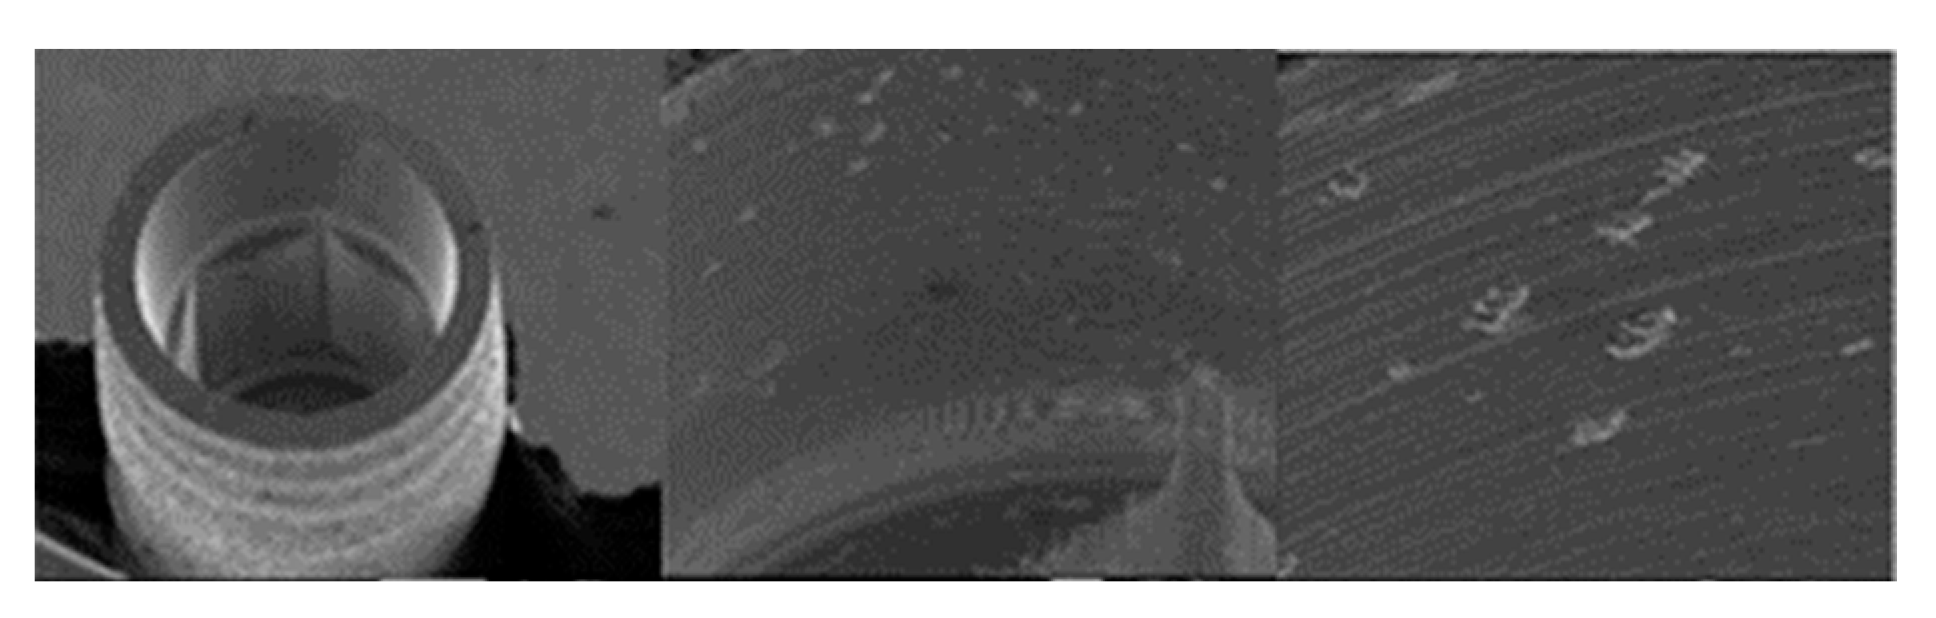

3.1.3. SK2 Implants

3.1.4. Vega Implants

4.1. SEM Evaluation